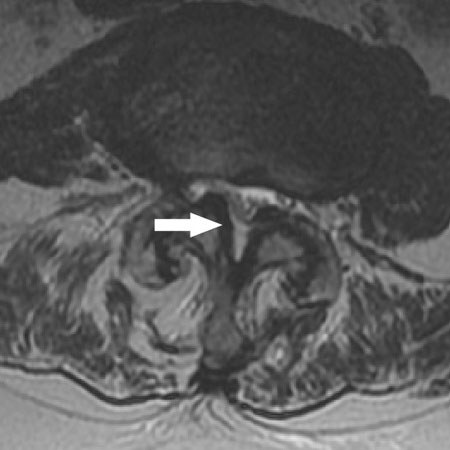

ხერხემლის სხეულის ღერძული ხედი, რომელიც აჩვენებს ცენტრალურ სპინალურ სტენოზს

BMJ 2008; 337:a2718; გამოიყენება ნებართვებით